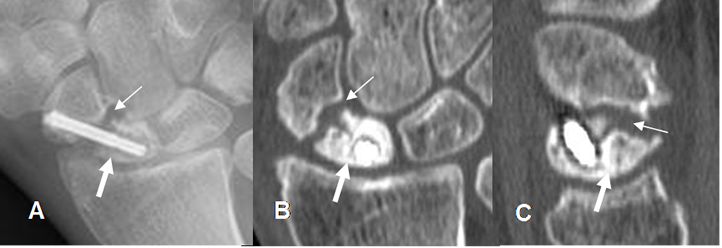

Fig 52 B. Seudoartrosis del escafoides.

A: Rx AP, B: TAC reconstrucción coronal y C: TAC reconstrucción sagital. Fractura del escafoides fijada con material de osteosíntesis. Se encuentra aumento del espacio entre los extremos, esclerosis de los bordes y ausencia de callo óseo, por la presencia de seudoartrosis. El polo inferior del escafoides es denso, por probable osteonecrosis. (Flechas gruesas).